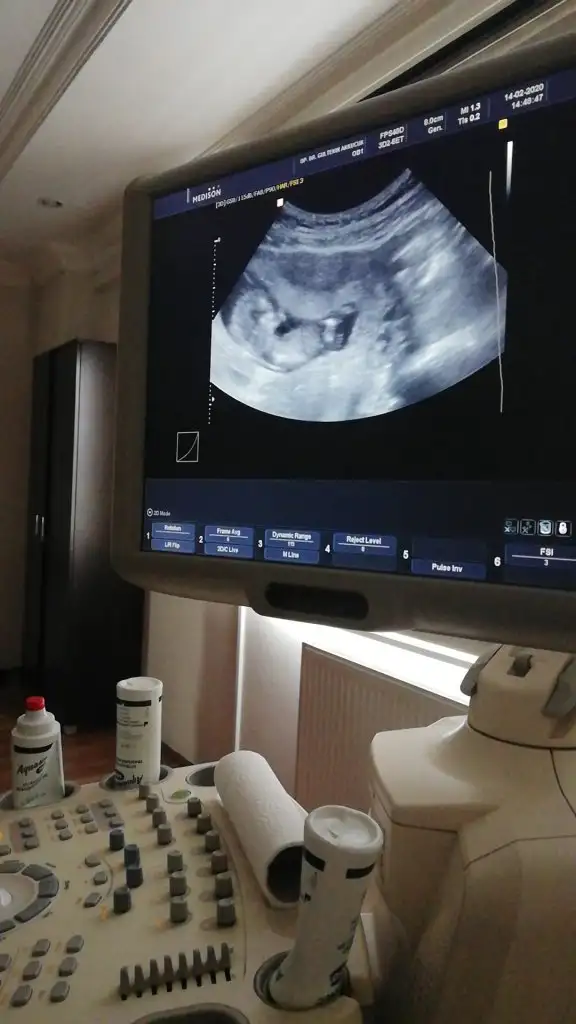

Bacak arası nubuda dik görünüyor erkek 11+2 dimi usg 12+ yada 13 olursa paylaşın A Aryaam

Evet sanki kız nette değilmiş usg

Dr. umda çok düşük ihtimal ile kız olabilir diye tahmin etti. Ama netlik için çok çok erken 2 hafta sonra netleşir dedi.

Bence de kızdır artık yanılma olmuyor bu haftalarda bacak arası boştu